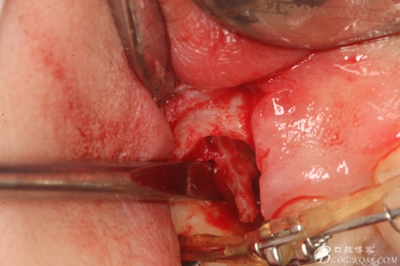

圖11.仔細(xì)考慮之后,在14頰側(cè)做垂直切口,切口長度僅達(dá)膜齦聯(lián)合處,做小切口。

圖12. 做垂直切口+齦溝內(nèi)切口,形成角形瓣,暴露出15根面。